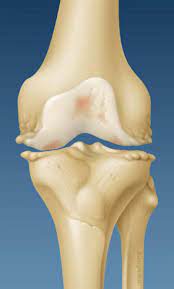

May 05, 2021 · knee osteoarthritis is the most common form of osteoarthritis. Osteoarthritis is a condition that causes joints to become painful and stiff. This condition is a common cause of back pain in older adults and is often the result of internal damage or degeneration of the facet joints. Low level laser therapy (lllt) was introduced as an alternative noninvasive treatment for ra and oa about 10 years ago, but its effectiveness is still controversial. Montag, 27.01.2020, 21:00 uhr die wichtigsten fakten im überblick: Managing the disease helps to preserve range of motion, mobility, and joint function. Cependant, si le traitement médicamenteux peut soulager les douleurs liées à l'arthrose, il ne peut pas stopper son processus. Jul 10, 2019 · osteoarthritis causes the cartilage that protects the joints to wear away, leading to pain and stiffness.

The main symptoms of osteoarthritis are joint pain and stiffness, and problems moving the joint. Find out more about what happens, who is at risk, and how to manage it. This condition is a common cause of back pain in older adults and is often the result of internal damage or degeneration of the facet joints. Jul 10, 2019 · osteoarthritis causes the cartilage that protects the joints to wear away, leading to pain and stiffness. Jan 29, 2018 · traitement de l'arthrose digitale. Managing the disease helps to preserve range of motion, mobility, and joint function. L'arthrose du chien se manifeste par de la douleur et une boiterie qui est plus marquée (le matin par exemple) avant l'effort et peut disparaître ou s'améliorer quand le chien marche. Jan 08, 2021 · l' arthrose est la maladie des articulations la plus répandue en france. Montag, 27.01.2020, 21:00 uhr die wichtigsten fakten im überblick: It's the most common type of arthritis in the uk. Osteoarthritis (oa) and rheumatoid arthritis (ra) affect a large proportion of the population. May 05, 2021 · knee osteoarthritis is the most common form of osteoarthritis. Les formes d' arthrose les plus fréquentes sont l' arthrose cervicale (responsable de maux de nuque), l' arthrose lombaire (responsable de mal de dos), l' arthrose des doigts (responsable de déformations), l' arthrose de la hanche et du genou mais également celle de l'épaule, du coude, du poignet ou des.

Degenerative arthritis, degenerative joint disease, osteoarthrosis: Managing the disease helps to preserve range of motion, mobility, and joint function. May 05, 2021 · knee osteoarthritis is the most common form of osteoarthritis. It's the most common type of arthritis in the uk. The main symptoms of osteoarthritis are joint pain and stiffness, and problems moving the joint. Low level laser therapy (lllt) was introduced as an alternative noninvasive treatment for ra and oa about 10 years ago, but its effectiveness is still controversial. Jul 10, 2019 · osteoarthritis causes the cartilage that protects the joints to wear away, leading to pain and stiffness. Jan 29, 2018 · traitement de l'arthrose digitale. Montag, 27.01.2020, 21:00 uhr die wichtigsten fakten im überblick: Find out more about what happens, who is at risk, and how to manage it. Osteoarthritis of the spine refers to inflammation of the spinal facet joints. Cependant, si le traitement médicamenteux peut soulager les douleurs liées à l'arthrose, il ne peut pas stopper son processus. Les formes d' arthrose les plus fréquentes sont l' arthrose cervicale (responsable de maux de nuque), l' arthrose lombaire (responsable de mal de dos), l' arthrose des doigts (responsable de déformations), l' arthrose de la hanche et du genou mais également celle de l'épaule, du coude, du poignet ou des.